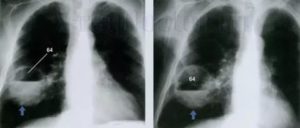

рентгенограмма левосторонней прикорневой пневмонии. Стрелками обозначена деформация легочного рисунка и отсутствие структуры корня (а). Через 2 месяца после пневмонии на фоне воспаления образовались фиброзные тяжи — карнификация (б)